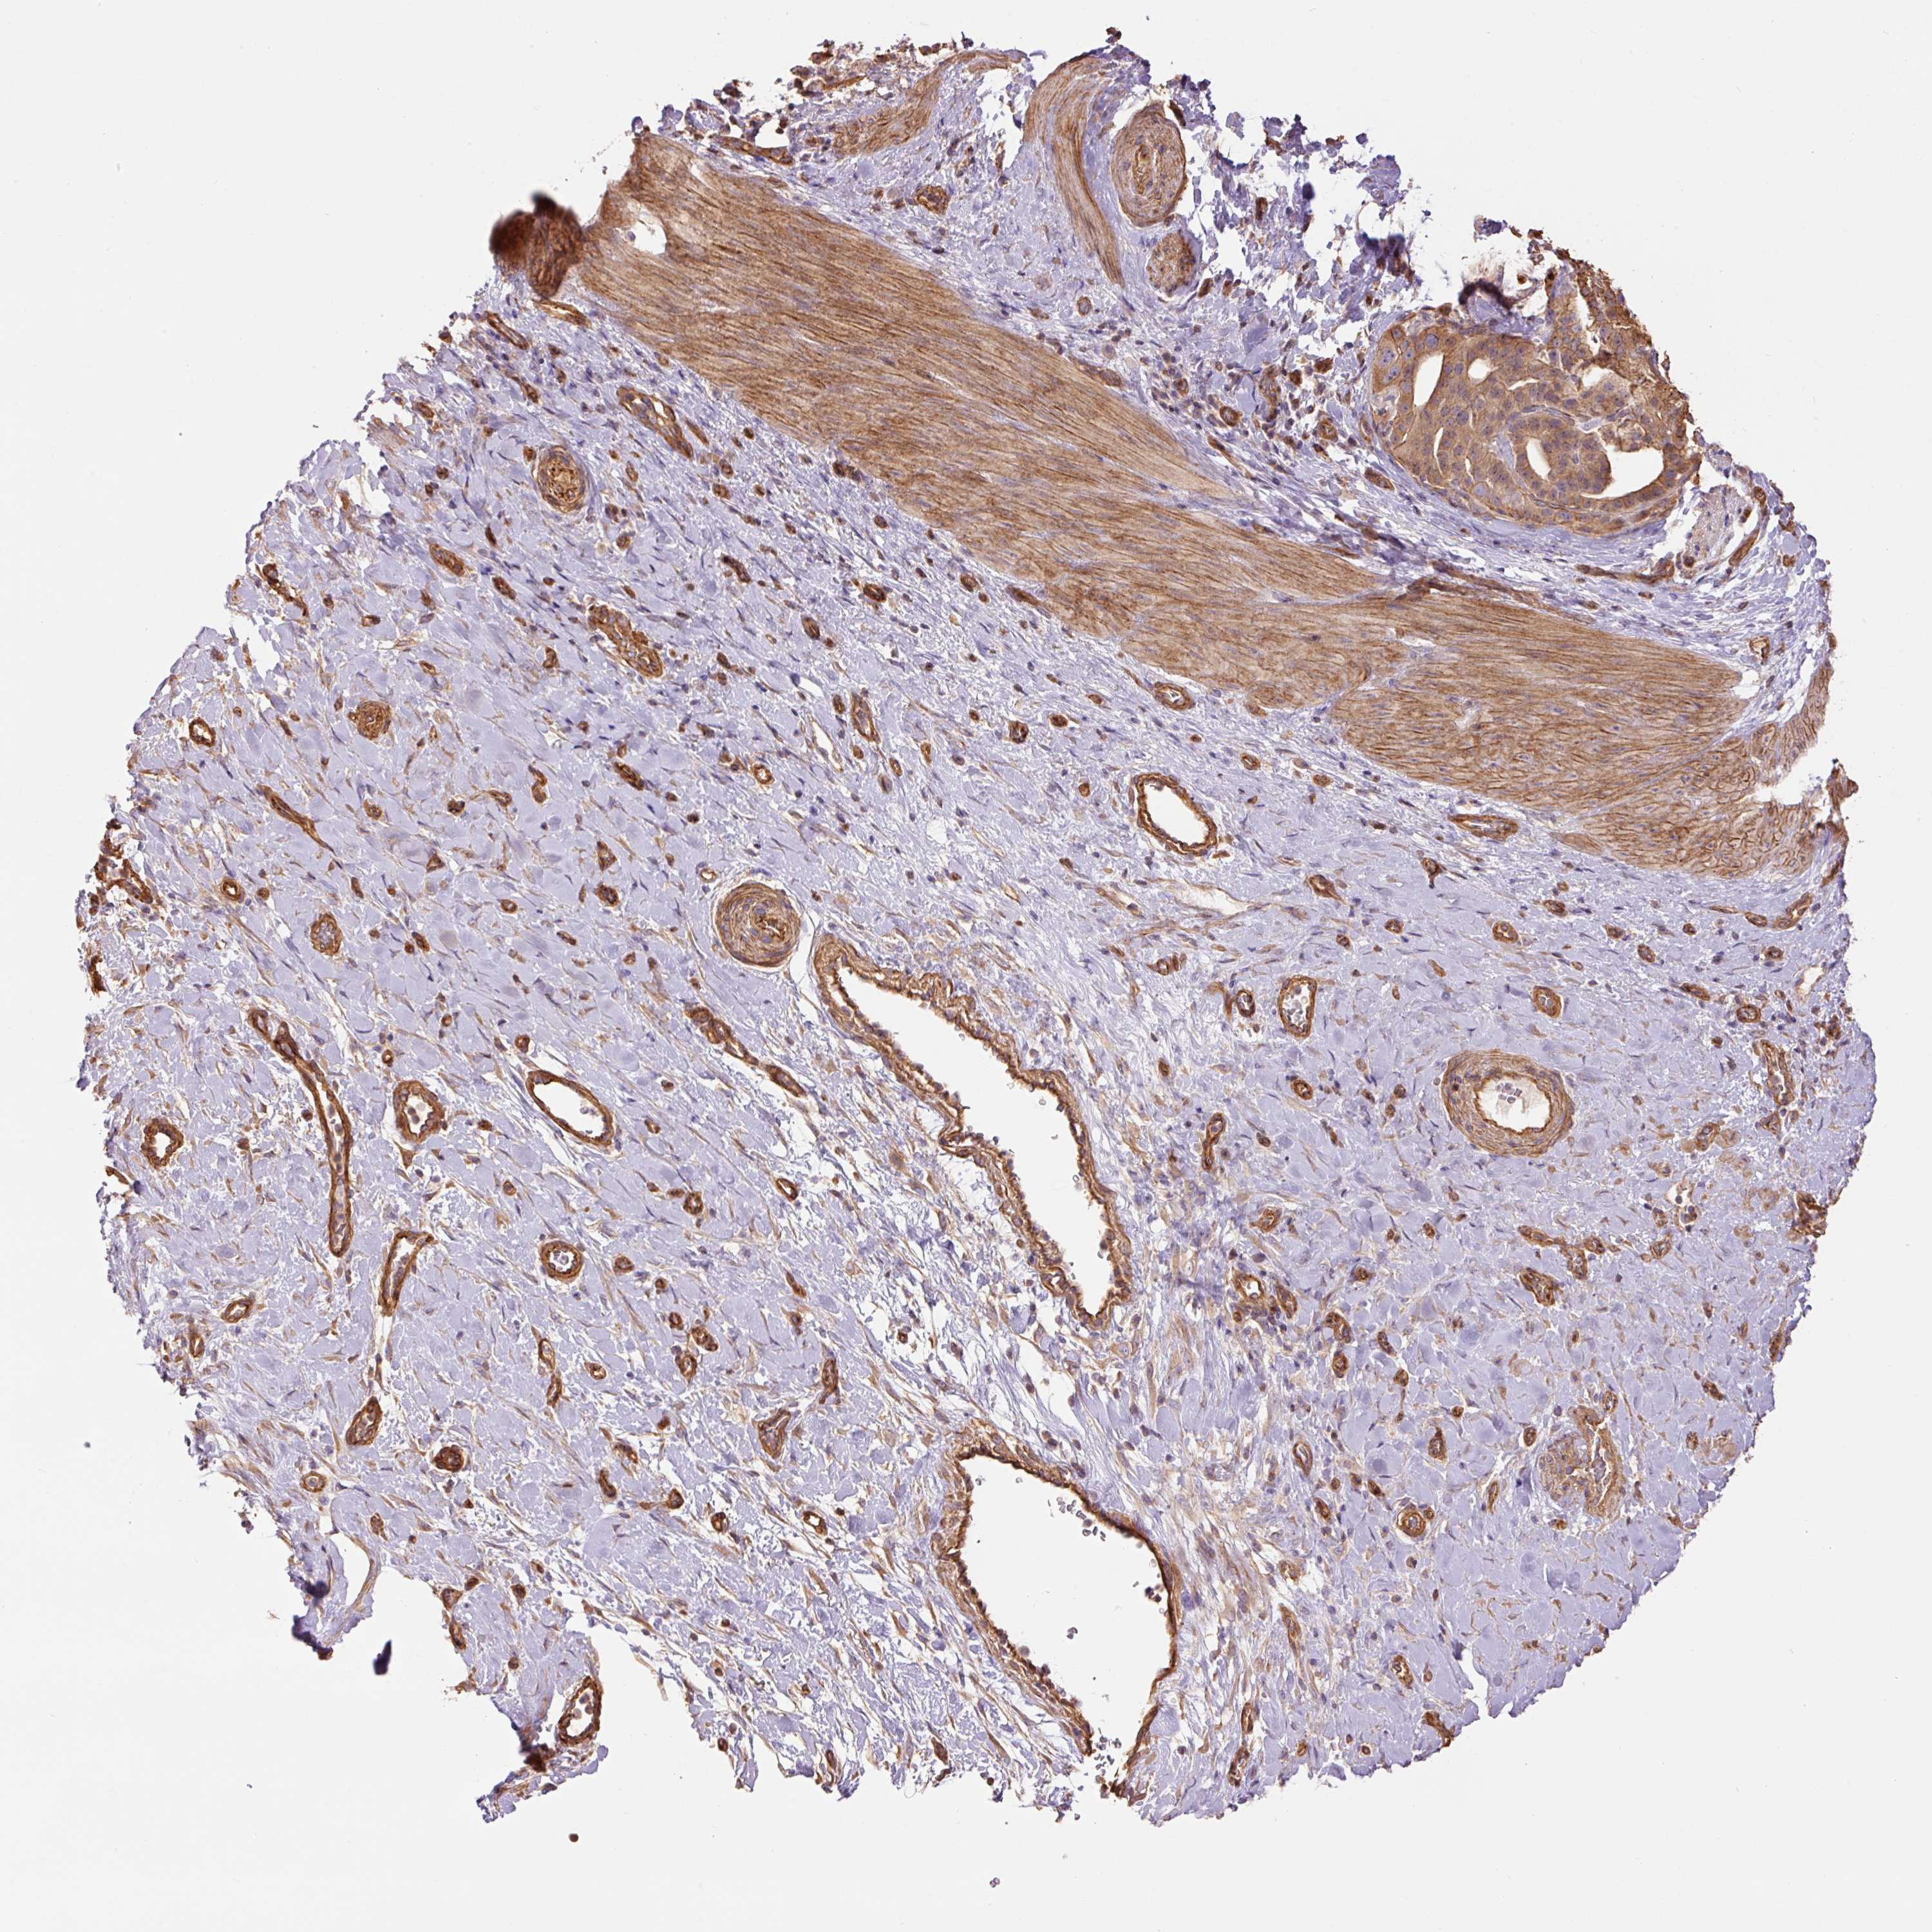

STOMACH CANCER - Protein expressioni

A mouse-over function shows sample information and annotation data. Click on an image to view it in a full screen mode. Samples can be filtered based on level of antibody staining by selecting one or several of the following categories: high, medium, low and not detected. The assay and annotation is described here.

Note that samples used for immunohistochemistry by the Human Protein Atlas do not correspond to samples in the TCGA dataset.

Antibody stainingi

Antibody staining in the annotated cell types in the current human tissue is reported as not detected, low, medium, or high, based on conventional immunohistochemistry profiling in selected tissues. This score is based on the combination of the staining intensity and fraction of stained cells.

Each image is clickable and will lead to virtual microscopy that enables deeper exploration of all samples and also displays staining intensity scores, fraction scores and subcellular localization as well as patient and tissue information for each sample.

Antibody HPA048630

Antibody HPA061142

Antibody CAB004026

Staining

High

Medium

Low

Not detected

Intensity

Strong

Moderate

Weak

Negative

Quantity

>75%

75%-25%

<25%

None

Location

Nuclear

Cytoplasmic/membranous

Cytoplasmic/membranous,nuclear

Adenocarcinoma, NOS

Adenocarcinoma, High grade